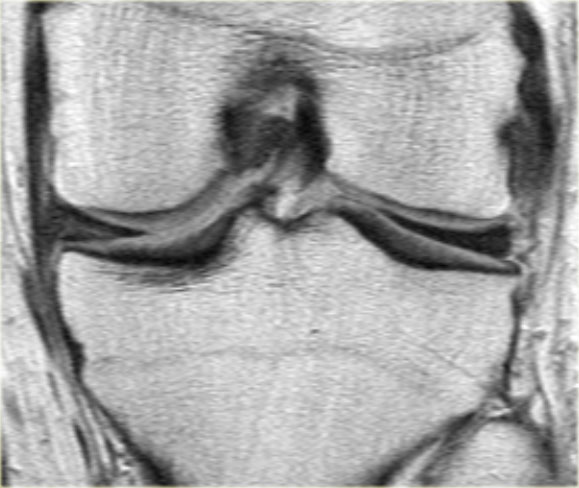

Cùng ca bệnh trên với hình ảnh mặt phẳng sagittal.

Lưu ý phần bị rách của sụn chêm chạy ra phía trước qua hố gian lồi cầu (các mũi tên)

- Thông thường chỉ có hai cấu trúc chạy trong hố gian lồi cầu. Ở đây chúng ta thấy dây chằng chéo sau bình thường.

- Dây chằng chéo trước bình thường.

- Phần bị rách của sừng sau như là ‘cấu trúc thứ ba’

trong hố gian lồi cầu. - Phần bị rách chạy ra phía trước.

- Phần bị rách nhập vào sừng trước và giả tạo hình ảnh rách dọc ở sừng trước.

Lưu ý phần còn lại nhỏ của sừng sau.

Bên trái là các hình ảnh PD sagittal của một trường hợp sụn chêm lật.

Toàn bộ sừng sau bị lật ra phía trước, tạo ra dấu hiệu sụn chêm rỗng (empty meniscus sign) (mũi tên).